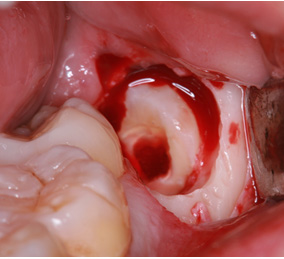

親知らずの歯根の先端と下顎神経が近接している場合は2回に分けて抜歯を行うことがあります。まず、親知らずを2分割して頭の部分を抜きます。その後しばらく期間をおいて、のこる歯根の部分が頭を抜いたスペースに移動したのを確認して抜きます。

このように2回に分ける事で安全な抜歯が可能です。

まず歯冠を切除し、疼痛がでないよう、冠部歯髄を除去してネオダイン(歯髄の鎮痛鎮静、象牙質の消毒、覆髄)を填入します。その後、粘膜骨膜弁にて完全閉鎖を行います。以下に処置の流れを示します。

歯冠切除量と歯根の移動量の結果です。術前の智歯(親知らず)の幅径に対して計測した智歯の長径の割合は1.21ポイント、術後は1.10ポイントで有意に差を認めました。数ヵ月待機することにより歯根は有意に近心側に移動していることを認めました。